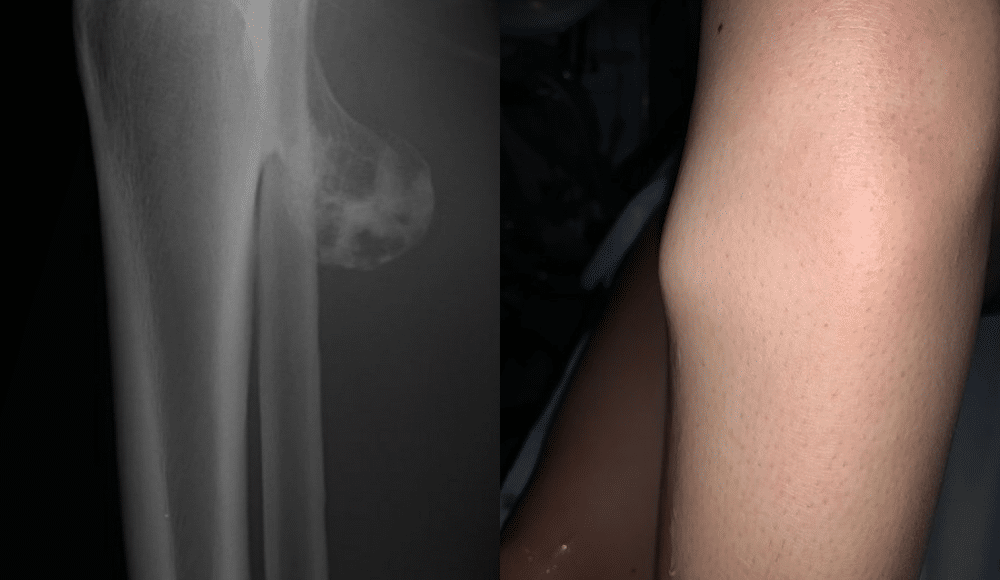

Osteocondroma em Raio-X (imagem: Shutterstock) e em paciente